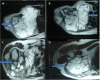

Figure 4. MRI of the right shoulder

T2 weighted axial images of right shoulder showing a lobulated hyperintense mass lesion that is totally replacing the right scapula and extending into the suprascapular region and invading subcutaneous soft tissues of the right chest wall, pleura, and lungs (A and B). The mass is extending to the superior aspect of the right shoulder (C), and right axillary region (D).